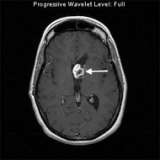

- Magnetic resonance imaging (MRI) is the preferred imaging technique for diagnosis.

This MRI image shows a juvenile pilocytic astrocytoma in the ventricle of the left frontal lobe (arrow). This patient had a partial removal of the tumor because the tumor involved the optic nerves.